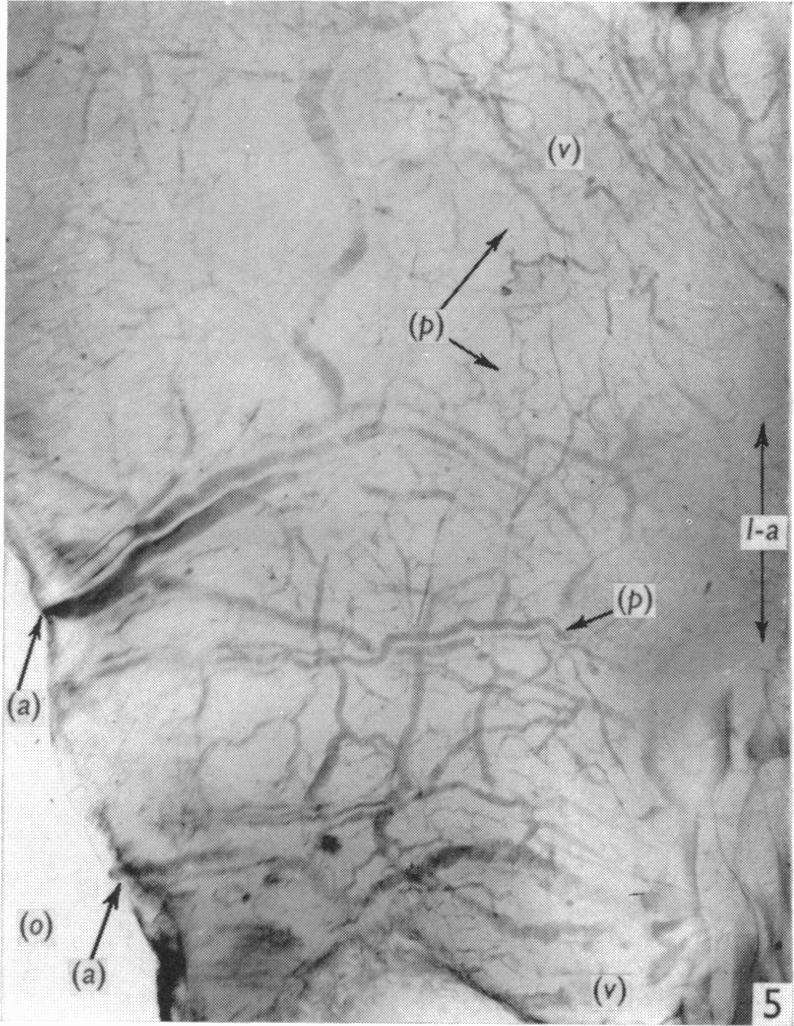

An x-ray microscopic study of the postnatal development of the vasa vasorum in the human aorta.

J Anat. 1965 Oct;99(Pt 4):877-89.

An x-ray microscopic study of the postnatal development of the vasa vasorum in the human aorta.人体主动脉中血管滋养管产后发育的X射线显微镜研究。